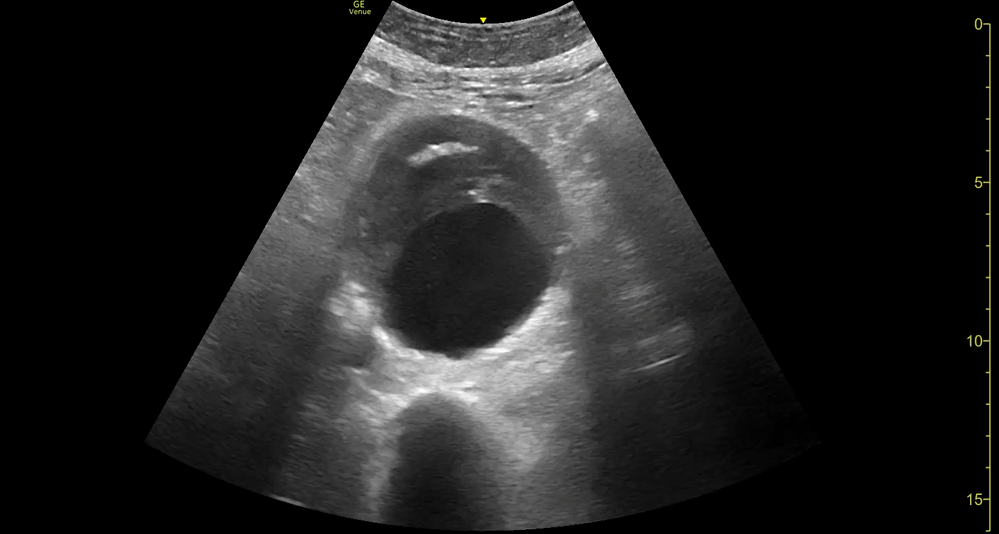

AAA

AAA GALLERY

AORTIC ANEURYSM

In adults, the normal anteroposterior aortic diameter is less than 2 cm, and 3 cm or more is considered dilated. The diameter of the common iliac arteries should not be more than 1.5 cm. Most AAAs occur below the renal arteries. As an aneurysm becomes larger it will dilate faster, leading to a greater risk of rupture. This risk remains low if the diameter is less than 5 cm. By contrast, there is a clear tipping point after surpassing 5.5 cm, as the annual incidence of rupture grows from <1% to 9.4% (5)

Once the aorta is identified, measure its diameter from outer to outer wall, as inner wall measurements may underestimate the diameter due to mural thrombus (false negative). While maintaining the transverse orientation, slide the probe distally until the aortic bifurcation and measure the diameter at its middle and distal portions. Then, rotate the probe to the longitudinal position, which is needed to identify saccular aneurysms. Attempt to obtain a view of the aorta that includes the origin of the coeliac trunk or SMA, and measure the AP diameter. Remember, AAA is not ruled out unless the entire length of the abdominal aorta can be visualized and measured.